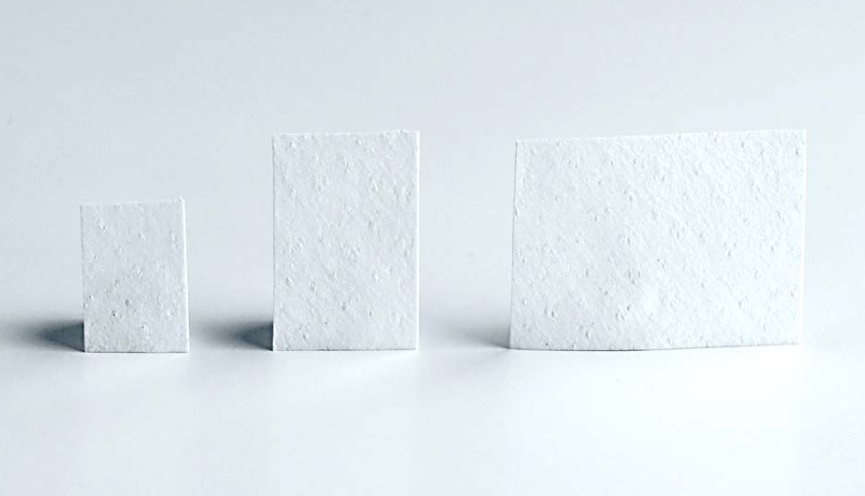

Bone Grafting Material - Microscopic Structure

طعوم عظمية

زراعة كتل عظمية للعيوب الكبيرة

تجديد موجّه

نمو عظمي بمساعدة الأغشية لنتائج دقيقة

مواد الطعم

مواد ترقيع ممتازة للاندماج الأمثل